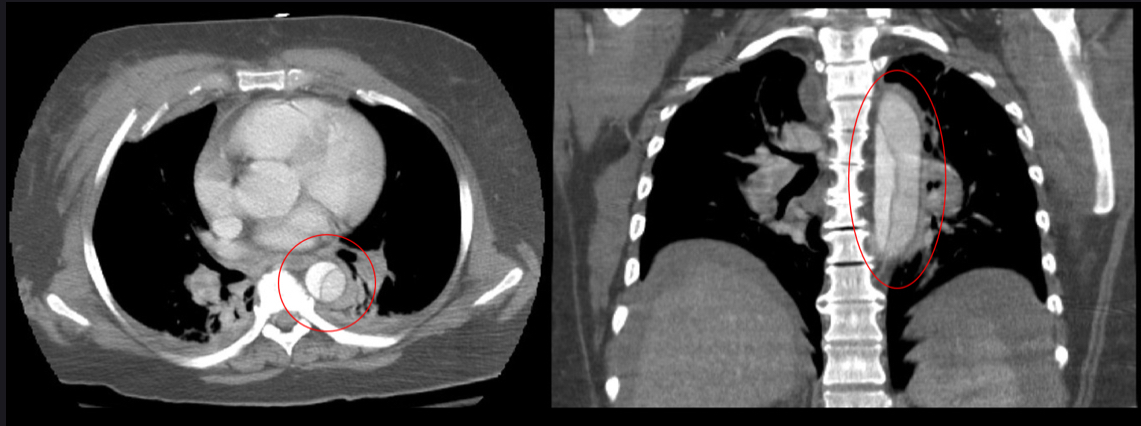

- CT angiogram diagnosis gold standard 1st line